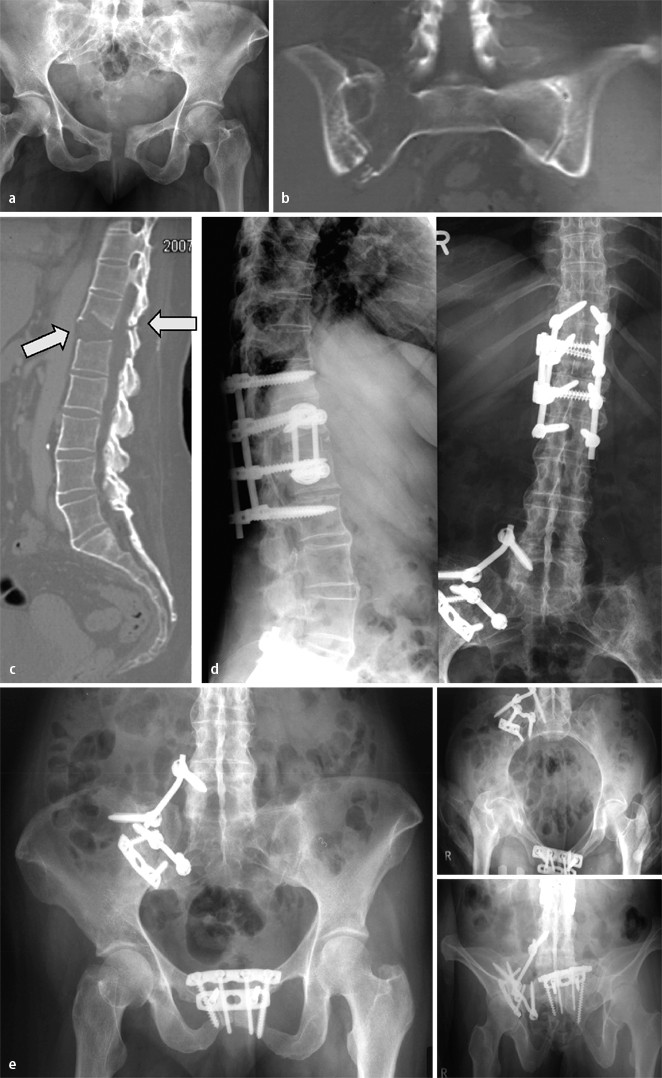

Fall 1, 32-jährige Patientin, AO-Fraktur 61B2.1., a a.-p. Beckenübersichtsaufnahme, b CT: Kompressionsfraktur der rechtsseitigen Massa lateralis, c a.-p. Beckenübersichtsaufnahme postoperativ, d,e Beckenübersichts- und Inlet-Aufnahme nach Entfernung des Fixateurs und Vollmobilisation, weitere Erläuterungen s. Kasuistik

Fall 2, 21-Jähriger mit isolierter bilateraler transforaminaler Sakrumfraktur AO 61C3.3), a Outlet- und Inlet-Aufnahme, b 3D-Oberflächenrekonstruktion in analoger Projektion, c CT-Nativschnitt und sagittale 2D-Rekonstruktion, d volumenorientierte Rekonstruktion, e a.-p., Inlet- und Outlet-Aufnahme nach Versorgung mit triangulärer bilateraler spinopelviner Transfixation, weitere Erläuterungen s. Kasuistik

Fall 3, 24-Jähriger mit isolierter Beckenringverletzung AO 62C1.3, a unzureichende a.-p. Aufnahme des Beckens, b CT mit koronarer Rekonstruktion: C-Verletzung mit vertikalem Versatz, Abriss des Querfortsatzes von LWK5 rechts, mehrfragmentärer Stauchungsfraktur des Sakrums, c offene Reposition, weitere Erläuterungen s. Kasuistik

Die 32-jährige Patientin war im europäischen Ausland gestürzt und nach Vorlage der a.-p. Beckenübersichtsaufnahme (Abb. 1 a) mit „stabiler“ isolierter vorderer Beckenringfraktur unter starken Beschwerden voll mobilisiert worden. Die rechtsseitige Sakrumfraktur wurde erst 10 Tage nach dem Trauma und der Rückkehr in die Heimat diagnostiziert (Abb. 1 b).

Die Fraktur wurde reponiert und mittels supraazetabulärem Fixateur externe und transiliosakraler Stellschraube stabilisiert (Abb. 1 c). In Abb. 1 d,e sind die Beckenübersichts- und Inlet-Aufnahme nach Entfernung des Fixateurs und Vollmobilisation dargestellt.

Fall 2

Bei dem 21 Jahre alten Mann lag eine isolierte bilaterale transforaminale Sakrumfraktur AO 61C3.3 („blow-out-fracture“) vor. Die Diagnose erfolgte mittels Outlet- und Inlet-Aufnahme, 3D-Oberflächenrekonstruktion in analoger Projektion, CT-Nativschnitt und sagittaler 2D-Rekonstruktion sowie volumenorientierter Rekonstruktion (Abb. 2 a–d).

Nach Reposition wurde die Verletzung mit triangulärer bilateraler spinopelviner Transfixation versorgt (Abb. 2 e).

Fall 3

Bei dem 24 Jahre alten männlichen Patienten war es bei einem Motorradunfall zu einer isolierten Beckenringverletzung (AO 62C1.3) gekommen. Die a.-p. Aufnahme des Beckens (Abb. 3 a) war lagerungs- und aufnahmetechnisch unzureichend. Die CT-Aufnahmen mit koronarer Rekonstruktion belegten eine C-Verletzung mit vertikalem Versatz sowie Abriss des Querfortsatzes von LWK5 rechts und eine mehrfragmentärer Stauchungsfraktur des Sakrums (Abb. 3 b).

Die Versorgung erfolgte durch offene Reposition der Sakrumfraktur mit winkelstabiler Platte und spinopelviner Transfixation bzw. supraazetabulärem Fixateur externe.